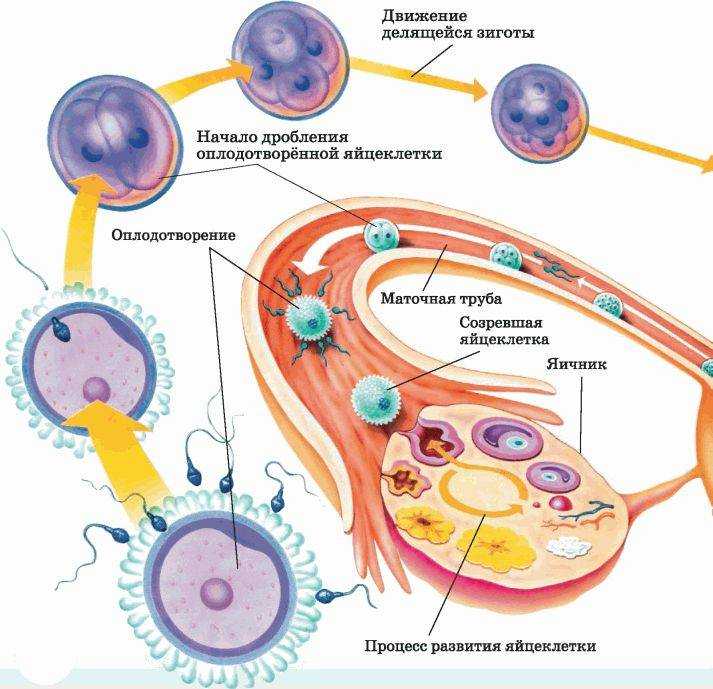

Созревание фолликула в яичнике: этапы и процессы